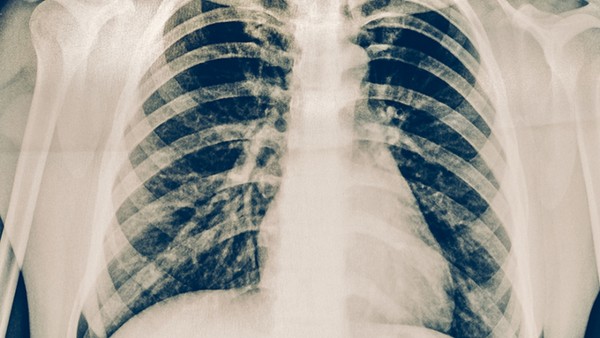

儿童病毒性肺炎应根据上述临床特点和实验室检查,鉴别病毒以外病原体引起的儿童肺炎、哮喘、支气管炎和气道异物。

轻症儿童经适当治疗后1-2周内恢复,可在门诊或家庭治疗,重症儿童需及时住院治疗中西医结合。